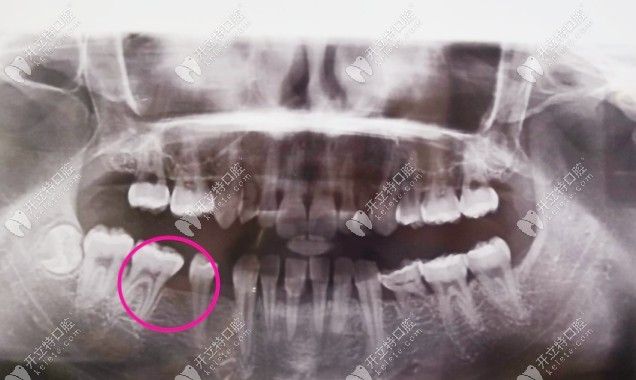

這是我到牙科拍的片子,大家應(yīng)該能看出來掉了兩顆吧,牙齒很不好,還有牙結(jié)石▼

牙齒拍片子的照片

醫(yī)生告訴我一顆牙齒的空隙已經(jīng)沒有辦法再安上一顆牙了,種植牙對于我來說確實(shí)分擔(dān)不了,所以就考慮了全瓷牙,靠近兩側(cè)的牙戴烤瓷牙套把縫填上。